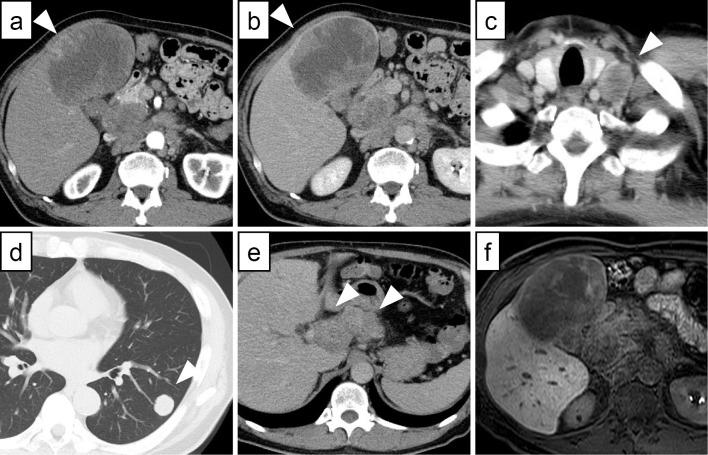

A 65-year-old man with hepatocellular carcinoma and lung metastasis was treated with a combination of atezolizumab and bevacizumab. Subsequently, the patient developed fever and new liver lesions, which were considered to indicate a pseudoprogression. Despite this, the treatment was continued. Three months later, computed tomography scans demonstrated that the new lesions had disappeared and both the primary tumor and metastases had shrunk. A partial response was achieved and maintained for two years. A histological examination revealed a predominance of CD8-positive lymphocytes and programmed death-ligand 1-positive tumor-associated macrophages, which may predict a positive response to this therapy. Pseudoprogression may therefore be a favorable prognostic factor in hepatocellular carcinoma.

一名65岁的肝细胞癌伴肺转移患者接受了阿替利珠单抗和贝伐单抗联合治疗。随后,患者出现发热和新的肝脏病变,被认为提示假性进展。尽管如此,治疗仍继续进行。三个月后,计算机断层扫描显示新病变消失,原发肿瘤和转移灶均缩小。获得了部分缓解并维持了两年。组织学检查显示CD8阳性淋巴细胞和程序性死亡配体1阳性肿瘤相关巨噬细胞占优势,这可能预示对该治疗有阳性反应。因此,假性进展可能是肝细胞癌的一个有利预后因素。